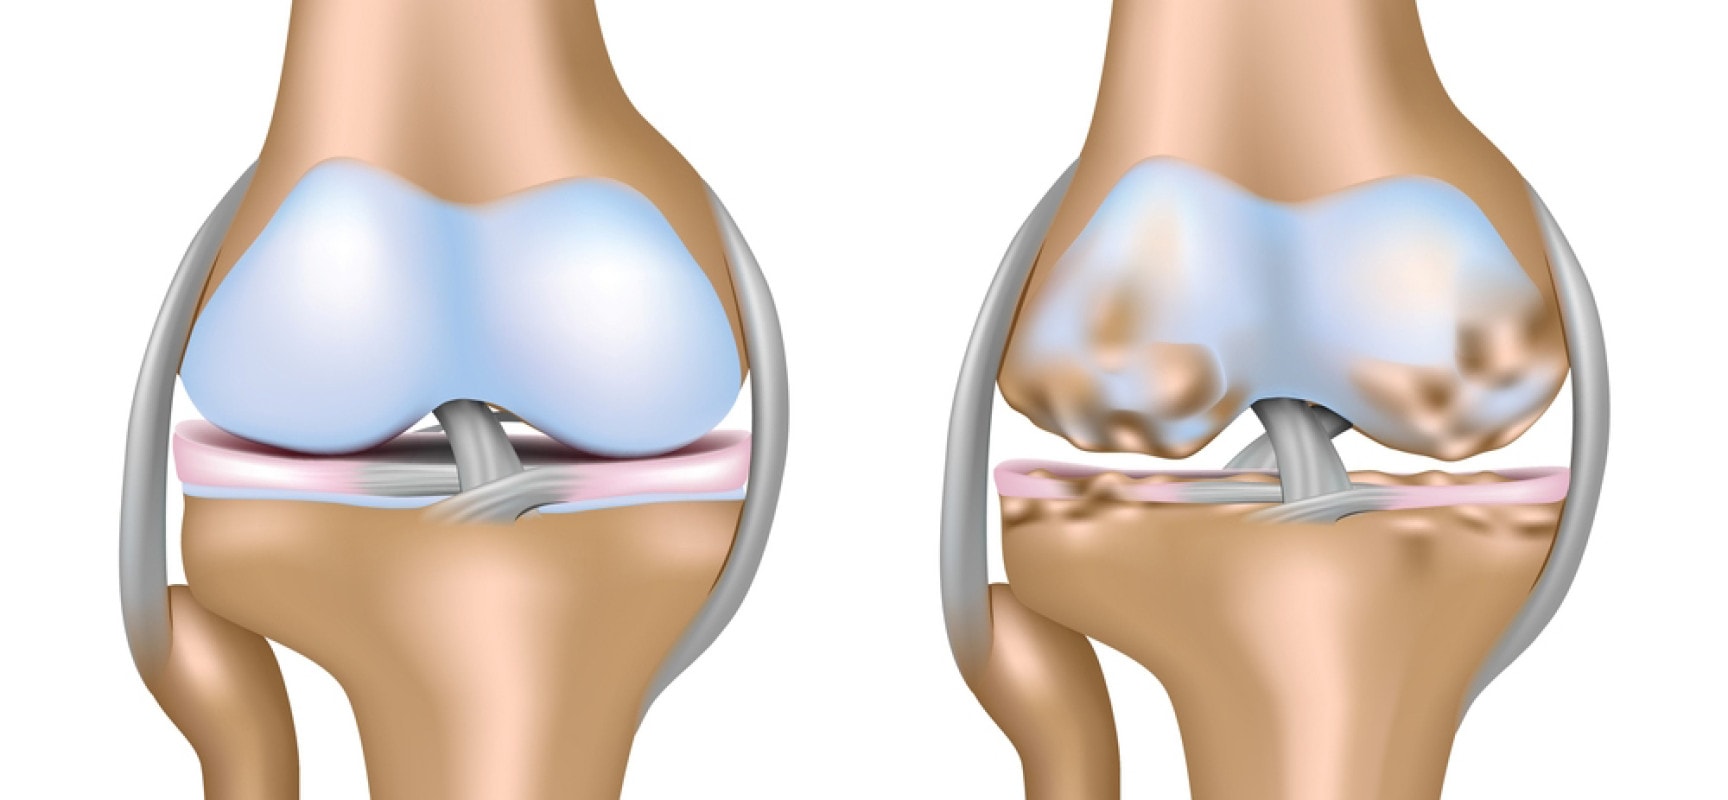

При гонартрозе первичные изменения в хряще начинаются на молекулярном и клеточном уровнях, после чего патологический процесс затрагивает гиалиновый хрящ. В зонах с наибольшей механической нагрузкой хрящ становится тусклым и мутным, затем истончается и начинает расслоение в разных направлениях. В тех участках, где хрящевая ткань исчезает, обнажается костная ткань. В ответ на утрату хряща кость уплотняется, происходит разрастание костной ткани по краям, образуются острые шипы (остеофиты), что приводит к деформации и искривлению ноги. Гонартроз коленных суставов также известен как остеоартроз или деформирующий артроз.

Обмен веществ в хрящевой ткани сустава происходит благодаря осмотическому давлению. При нагрузке на хрящ выделяется смазка, а при разгрузке она впитывается обратно. Таким образом, во время движений осуществляется питание суставного хряща. Если из-за повышенных механических нагрузок хрящ не восстанавливается полностью, обменные процессы в тканях нарушаются, и в тех местах, где хрящ колена испытывает наибольшее давление, он начинает постепенно истончаться. У пациента нарушается структура коллагеновых волокон, хрящ теряет свои амортизационные свойства, происходит размягчение хряща (хондромаляция) и нарушается функция хондроцитов. При гонартрозе суставной хрящ теряет свою физиологическую эластичность и прочность.

В коленном суставе нарушается конгруэнтность. Из-за увеличенного синтеза костного вещества формируются костные разрастания в виде остеофитов, которые раздражают синовиальную оболочку, вызывая воспаление. Все эти патологические изменения приводят к ограничению подвижности в суставе.